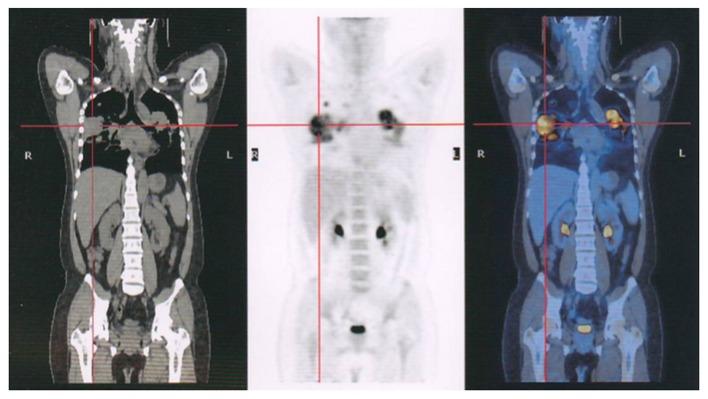

The aim of the present study was to evaluate the sensitivity of positron emission tomography/computed tomography (PET/CT) in the diagnosis of giant cell tumor of the bone (GCTB) using the maximum standard uptake value (SUVmax), which indicates the metabolic rate of tissue. Patients diagnosed with pathologically confirmed GCTB between January 2006 and July 2015 were included in the study. Data from PET/CT scans and pathological and clinical reports for all patients were retrospectively reviewed. The SUVmax value from the PET/CT scan of each patient was retrieved and analyzed. A total of 20 patients [12 male and 8 female; age range, 12-45 years; mean age ± standard deviation (SD), 33.5±15.7] with complete PET/CT data and a pathologically and clinically confirmed diagnosis were examined. The SUVmax of GCTB was between 1.8 and 18.6, with a mean ± SD of 9.2±3.8. Although GCTB is not considered to be a malignant lesion, PET/CT scans of the tumors reveal high-grade malignant osseous sarcomas. It is, therefore, important not to mistake such lesions for osteosarcomas or metastatic malignancies of the bone.

本研究的目的是使用最大标准摄取值(SUVmax)评估正电子发射断层扫描/计算机断层扫描(PET/CT)在骨巨细胞瘤(GCTB)诊断中的敏感性,该值表明组织的代谢率。本研究纳入了2006年1月至2015年7月期间经病理确诊为GCTB的患者。对所有患者的PET/CT扫描数据以及病理和临床报告进行了回顾性分析。获取并分析了每位患者PET/CT扫描的SUVmax值。共检查了20例具有完整PET/CT数据且经病理和临床确诊的患者[12例男性和8例女性;年龄范围为12 - 45岁;平均年龄±标准差(SD)为33.5±15.7]。GCTB的SUVmax在1.8至18.6之间,平均±SD为9.2±3.8。尽管GCTB不被认为是恶性病变,但肿瘤的PET/CT扫描显示为高级别恶性骨肉瘤。因此,重要的是不要将此类病变误诊为骨肉瘤或骨转移性恶性肿瘤。